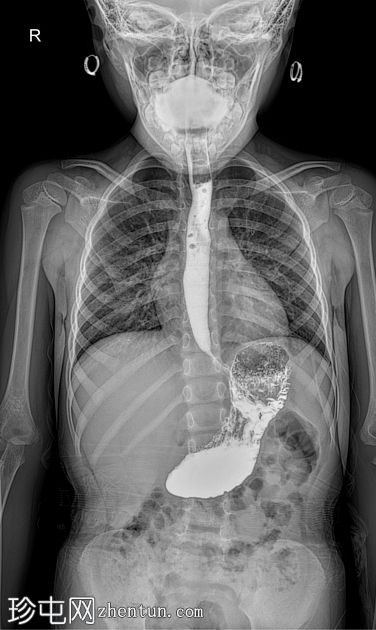

荧光透视

AP

食管体扩张,远端食管平滑收窄,呈现经典的鸟嘴状或鼠尾状外观

扩张食管内可见气液平面

造影剂进入胃排空延迟

荧光透视钡餐检查显示食管扩张,胃食管连接处平滑收窄,造影剂进入胃延迟。虽然这些特征提示贲门失弛缓症,但并非其特征性表现,尤其是在儿童中,因为下食管括约肌狭窄有时可视为正常变异。

贲门失弛缓症在儿科人群中并不常见,但对于年龄较大且存在非特异性上消化道症状的儿童,例如吞咽固体和液体食物困难、反流、体重下降或反复食物潴留,则应考虑该病。可能支持诊断的影像学征象包括:

食管均匀扩张

原发性蠕动消失

排空延迟

食管远端平滑收窄

荧光透视被认为是评估疑似贲门失弛缓症的一线影像学检查方法。